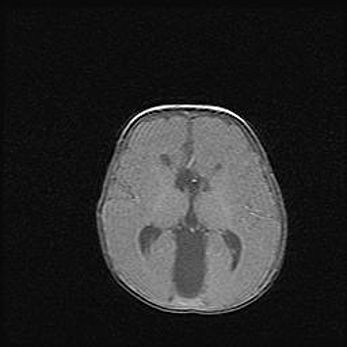

Открытая гидроцефалия.

Возраст: 9 месяцев 12 дней

Вес: 6800 г

Пол: мужской

Окружность головы: 41,5 см

Срок гестации: 28 недель

Гидроцефалия головного мозга у новорожденных имеет характерный признак: опережающий рост окружности головы приводит к визуально хорошо определяемой гидроцефальной форме сильно увеличенного в объёме черепа. Детские неврологи определяют следующие симптомы гидроцефалии у грудничков: выбухающий напряжённый родничок, частое запрокидывание головы, смещение глазных яблок к низу.